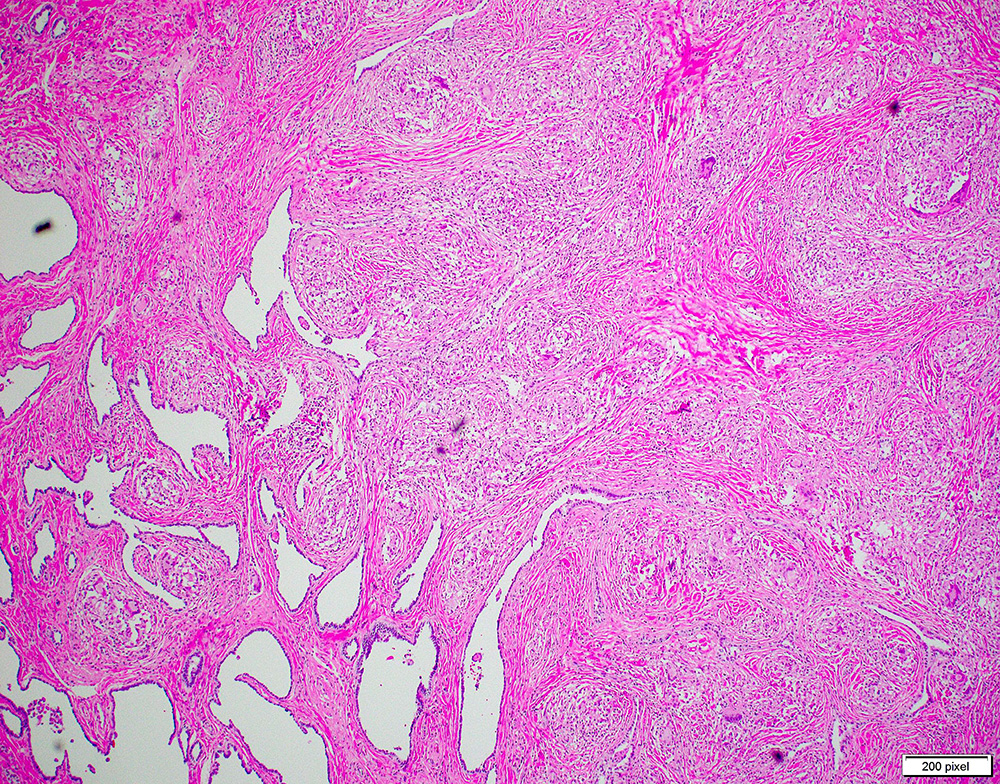

Testicular Mass

A 27-year-old African-American male presented with painful left testicular mass. He noticed a slight fluctuation in the size of the mass over the past four months, as well as subjective fever and chills. He denied dysuria, discharge, and gross hematuria. Initial workup revealed a mildly elevated alpha-fetoprotein (AFP) level (350 U/L) with normal beta-HCG and LDH.

Ultrasound exam revealed a 1.6 cm hypoechoic left testicular mass and a 0.6 cm right testicular mass.

Patient has a past medical history significant for epididymitis status post partial antibiotic treatment complicated by medication noncompliance a year ago. He underwent left radical orchiectomy.